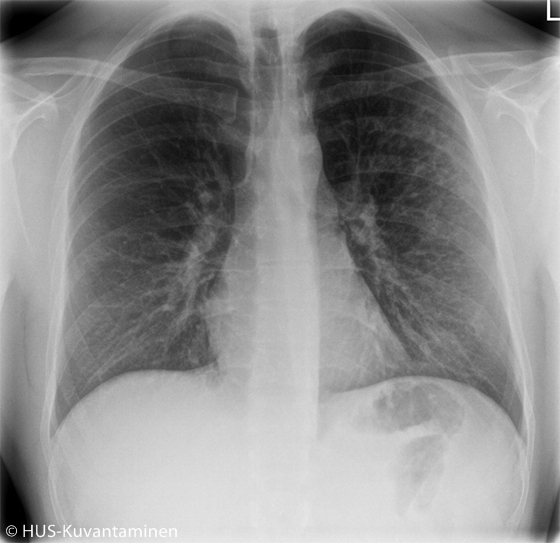

Atypical pneumonia in a patient with HIV (radiograph without markers).

A young man had been coughing and experiencing low-grade fever for 2 weeks. The patient had HIV, which had been managed appropriately. Obstruction was heard in pulmonary auscultation.

Picture: HUS Imaging